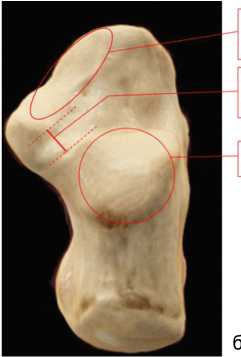

Клинический пример группы исследования

Пациент 1996 года рождения поступил в ННИИТО им. Я.Л. Цивьяна с жалобами на деформацию обеих стоп, боли в стопах, усиливающиеся после физических нагрузок, больше — справа. Из анамнеза известно, что деформация обеих стоп беспокоит пациента с детства. Наблюдался у травматолога-ортопеда в поликлинике по месту жительства, консервативная терапия оказалась неэффективной. В течение последних нескольких лет пациент отмечал нарастание болевого синдрома и дискомфорта в стопах, больше — справа, трудности ношения обуви, в связи с чем обратился в НИИТО. На основании жалоб, анамнеза, данных клинического и рентгенологического исследований установлен диагноз: приобретенная плосковальгусная деформация обеих стоп 2–3-й степени справа, 2-й степени слева; Hallux valgus bilateralis 1–2-й степени; синдром двусторонней таразалгии, больше — справа.

По результатам рентгенографического исследования голеностопного сустава до хирургического лечения пяточно-подошвенный угол составлял 17º, таранно-первоплюсневый в прямой проекции — 9º, в боковой проекции — 6º.

Проведено предоперационное планирование и хирургическое лечение с использованием предлагаемого метода. У пациента определены суставные фасетки типа А, расстояние от пяточно-кубовидного сустава — 1,5 см, угол наклона линии остеотомии относительно наружной стенки пяточной кости — 100º (рис. 5). По данным МСКТ, на следующий день после хирургического лечения ни одна суставная фасетка не была повреждена, угол наклона остеотомии отличался от запланированного на 1°. Расстояние от пяточно-кубовидного сустава отличалось на 1 мм (рис. 6).

Рис. 5. Схема предоперационного планирования на основании 3D-модели пяточной кости

Через год после хирургического лечения повторно проведено рентгенологическое исследование голеностопного сустава с нагрузкой в двух проекциях, на которых повторно измерили пяточно-подошвенный угол (20º), таранно-плюсневый угол в прямой проекции (3º) и в боковой проекции (3º). На контрольном приеме через год опрос по AOFAS показал изменение значений с 42 баллов до операции до 89 баллов после операции.